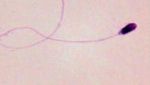

Jakarta - Kamu mungkin sudah punya bayangan seperti apa bentuk sperma dari gambar atau ilustrasi. Tapi bagaimana sih tampilannya bila dilihat langsung? Simak di sini.

Penampakan Sperma di Bawah Mikroskop, Ini Beda yang Sehat Vs Abnormal